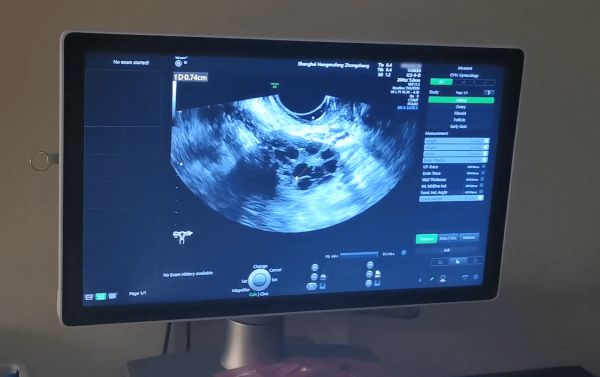

流产会对女性的子宫造成损伤,进而导致子宫内膜变薄和宫腔粘连等问题,还可能会因为护理不当导致炎症感染,出现输卵管堵塞、粘连等问题。

提醒有过流产经历的女性备孕前,先做好孕前检查,排查身体的健康状况,尤其要重点排查子宫和输卵管,如发现不利于怀孕问题,及时针对性治疗处理,才能顺利怀孕生子。